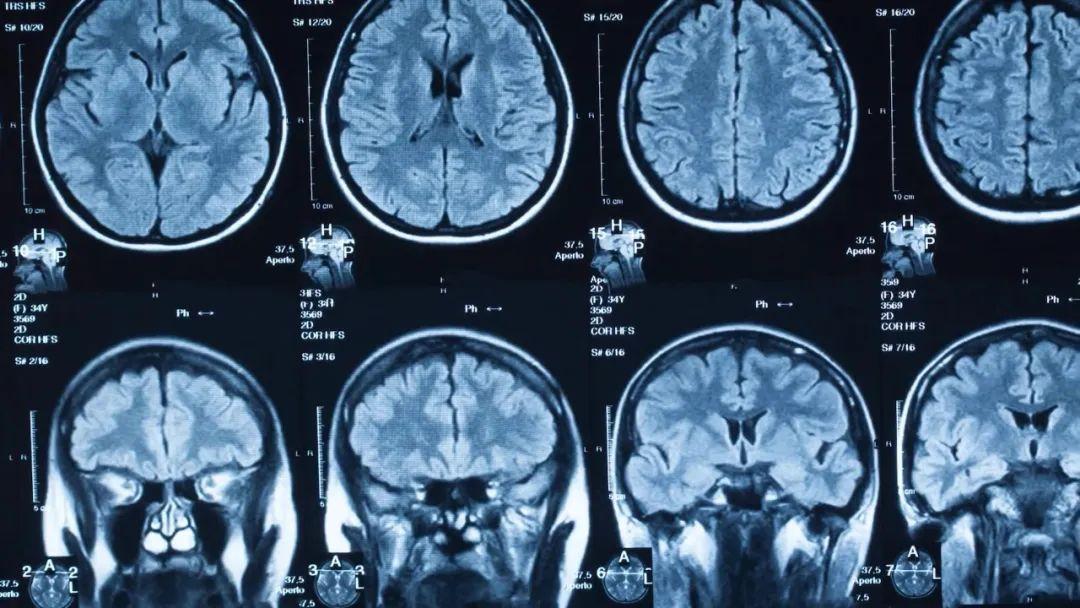

对于人体中的核磁共振成像,通常以氢核为目标,因为其中水和脂肪中有很多,然后图像的亮度基本上可以告诉我们脂肪和水的数量。人们也可以瞄准其它原子核并进行测量,这就导致了不同核磁共振图像的工作方式不同。核磁共振成像非常适合于检查软组织,而对于骨折一般则使用X射线成像。

如果有在强磁场中自旋的原子核,那么它们的自旋将与磁场对齐。假设我们有一个指向z方向的恒定且均匀的磁场,那么核自旋也将优先指向z方向。然而,由于热运动的存在,这会出现一些偏差,有一些原子核的自旋方向甚至与z方向相反。所有原子核的净磁矩称为磁化强度,它最终将指向z方向。在核磁共振机器中,z方向一般是从头到脚的方向。

上述提到,共振频率与磁场强度成正比,正因为如此,我们可以使用磁场梯度来瞄准特定位置的原子核,生成不同位置的身体切片图像。